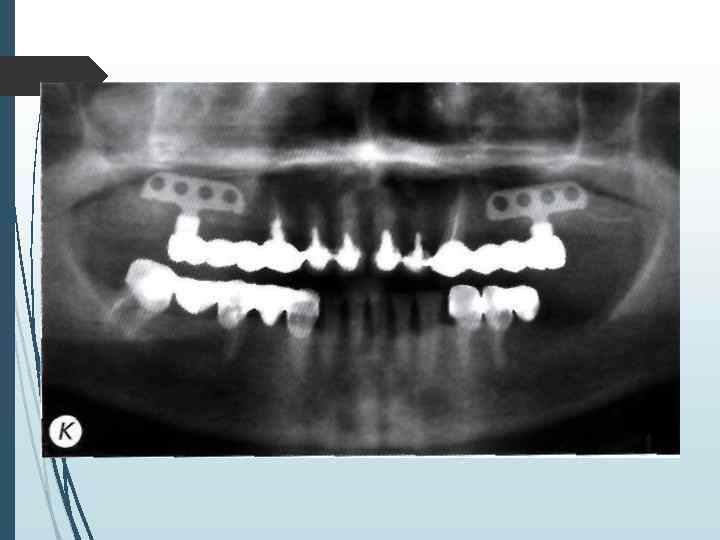

Определение количества имплантатов При одиночных дефектах зубных рядов применяют принцип имплантационной изотопии, обоснованный С Mnratori. Суть его сводится к следующему положению: количество устанавливаемых имплантатов должно соответствовать количеству отсутствующих корней зубов. Исходя из этого принципа, при одиночных дефектах фронтальной группы зубов (включая премоляры) необходимо устанавливать один имплантат, при отсутствии моляра два имплантата Исключение составляютслучаи, когда вследствие конвергенции сосед них с дефектом зубов отсутствует пространство, необходимое для установки двух имплантатов Ватой ситуации можно установить один имплантат на место двух-трехкорневого зуба, но диаметр имплантата при атом должен составлять но меньшей мере 4 мм (лучше

При включенных дефектах может устанавливаться различное количество имплантатов. которое определяется не столько видом адентии, сколько конструкцией протеза и анатомическими условиями. При включении в протезную конструкцию граничащих с дефектомзубов наиболее распространенным вариантом является установка одного-двух винтовых или цилиндрических имплантатов или одного пластиночного имплантата. или одного имплантата комбинированной формы При использовании в качестве опоры зубного протеза только имплантатов лучше придерживаться принципа имилантационной изотопии или использовать формулу расчета: X = N 1. где X — оптимальное количество имплантатов. А' количество отсутствующих корней зубов.